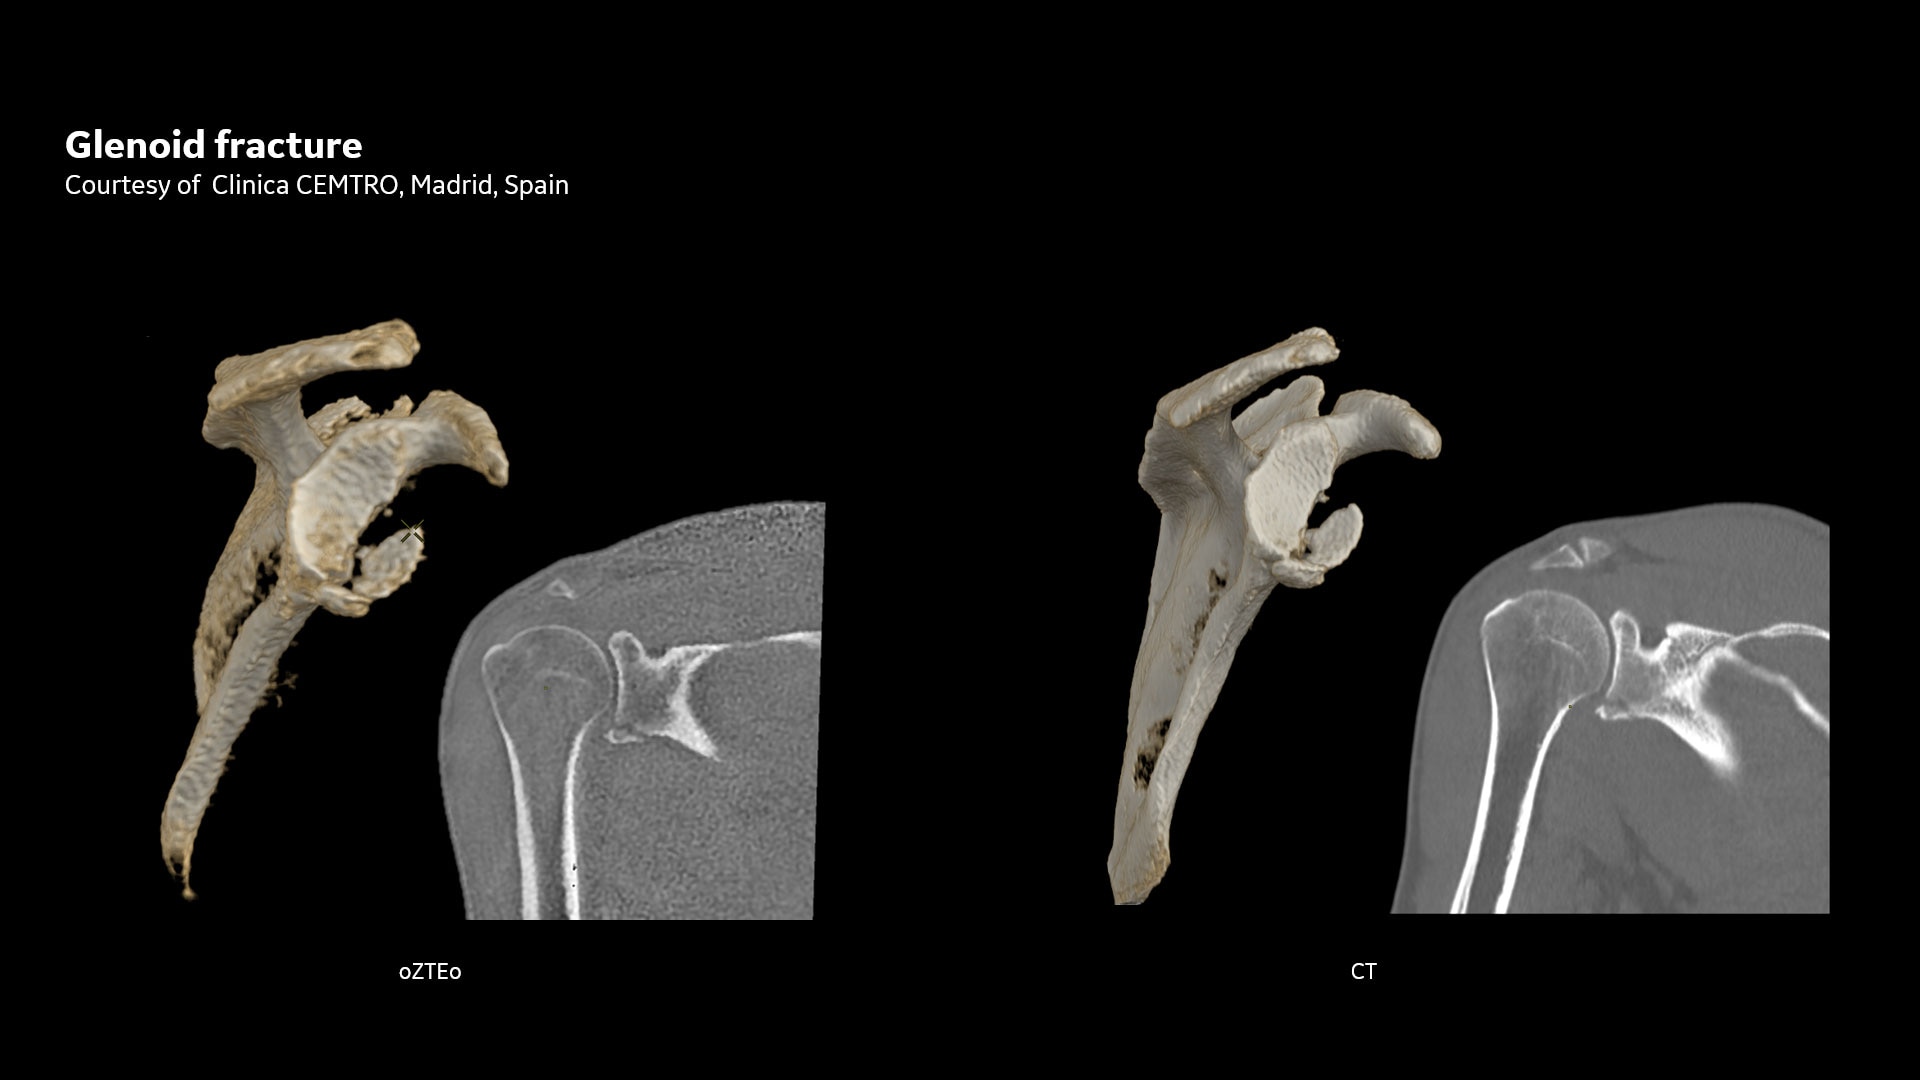

oZTEo ist für alle Anatomien ohne ionisierende Strahlung verfügbar und liefert dabei Bilder von Knochenmorphologie, Verkalkungen, Verknöcherungen und Frakturen. OZTEo ergänzt die herkömmliche MRT-Weichteilgewebeuntersuchung mit perfekter Anpassung und bietet isotropische 3D-Bildgebung unter Verwendung einer radialen ZTE-Erfassung (Zero TE) mit inhärenter Unempfindlichkeit bei Bewegungen. Verwendung von oZTEo mit Volumenbeleuchtung für realistisches 3D-Rendering.

Mit dieser neuen Anwendung zur Darstellung von kortikalen Knochenoberflächen, basierend auf der radialen ZTE-Anwendung, können Sie eine neue Möglichkeit für die Knochenbildgebung anbieten und einen erheblichen klinischen Nutzen für Ihre orthopädischen Untersuchungen gewinnen.

Leistungsstarke Knochenbildgebung für alle Anatomien